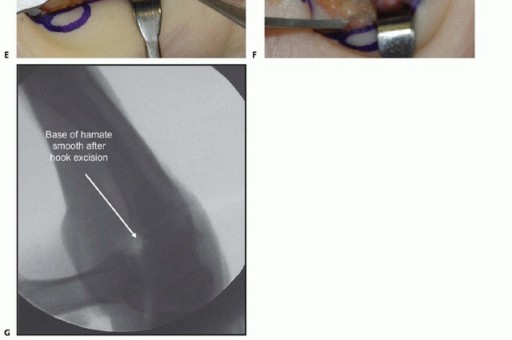

More commonly, surgeons encounter symptomatic nonunions of the hamate hook. In these chronic cases, excision of the ununited fragment is the gold standard, offering reliable pain relief and a rapid return to function without significant biomechanical compromise. Utilizing the same volar approach, the ununited hook fragment is identified. Dissection must stay strictly subperiosteal on the hook to avoid injury to the deep motor branch of the ulnar nerve, which curves intimately around its base. The transverse carpal ligament and the pisohamate ligament are sharply detached from the fragment. The fragment is then excised, and the remaining base on the hamate body is smoothed with a rongeur or a high-speed burr to prevent future flexor tendon fraying or rupture.

Clinical & Radiographic Imaging Archive